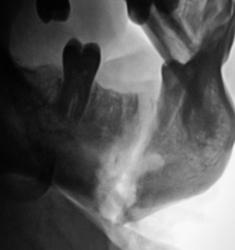

Сегодня, пациент направлен в рентгеновский кабинет для рентгенографии нижней челюсти с диагнозом "остеомиелит". Произведена рентгенография.

Ваше мнение уважаемые коллеги?

перелом нижней челюсти. Видна секвестральная полость, участки деструкции кости - остеомиелит.